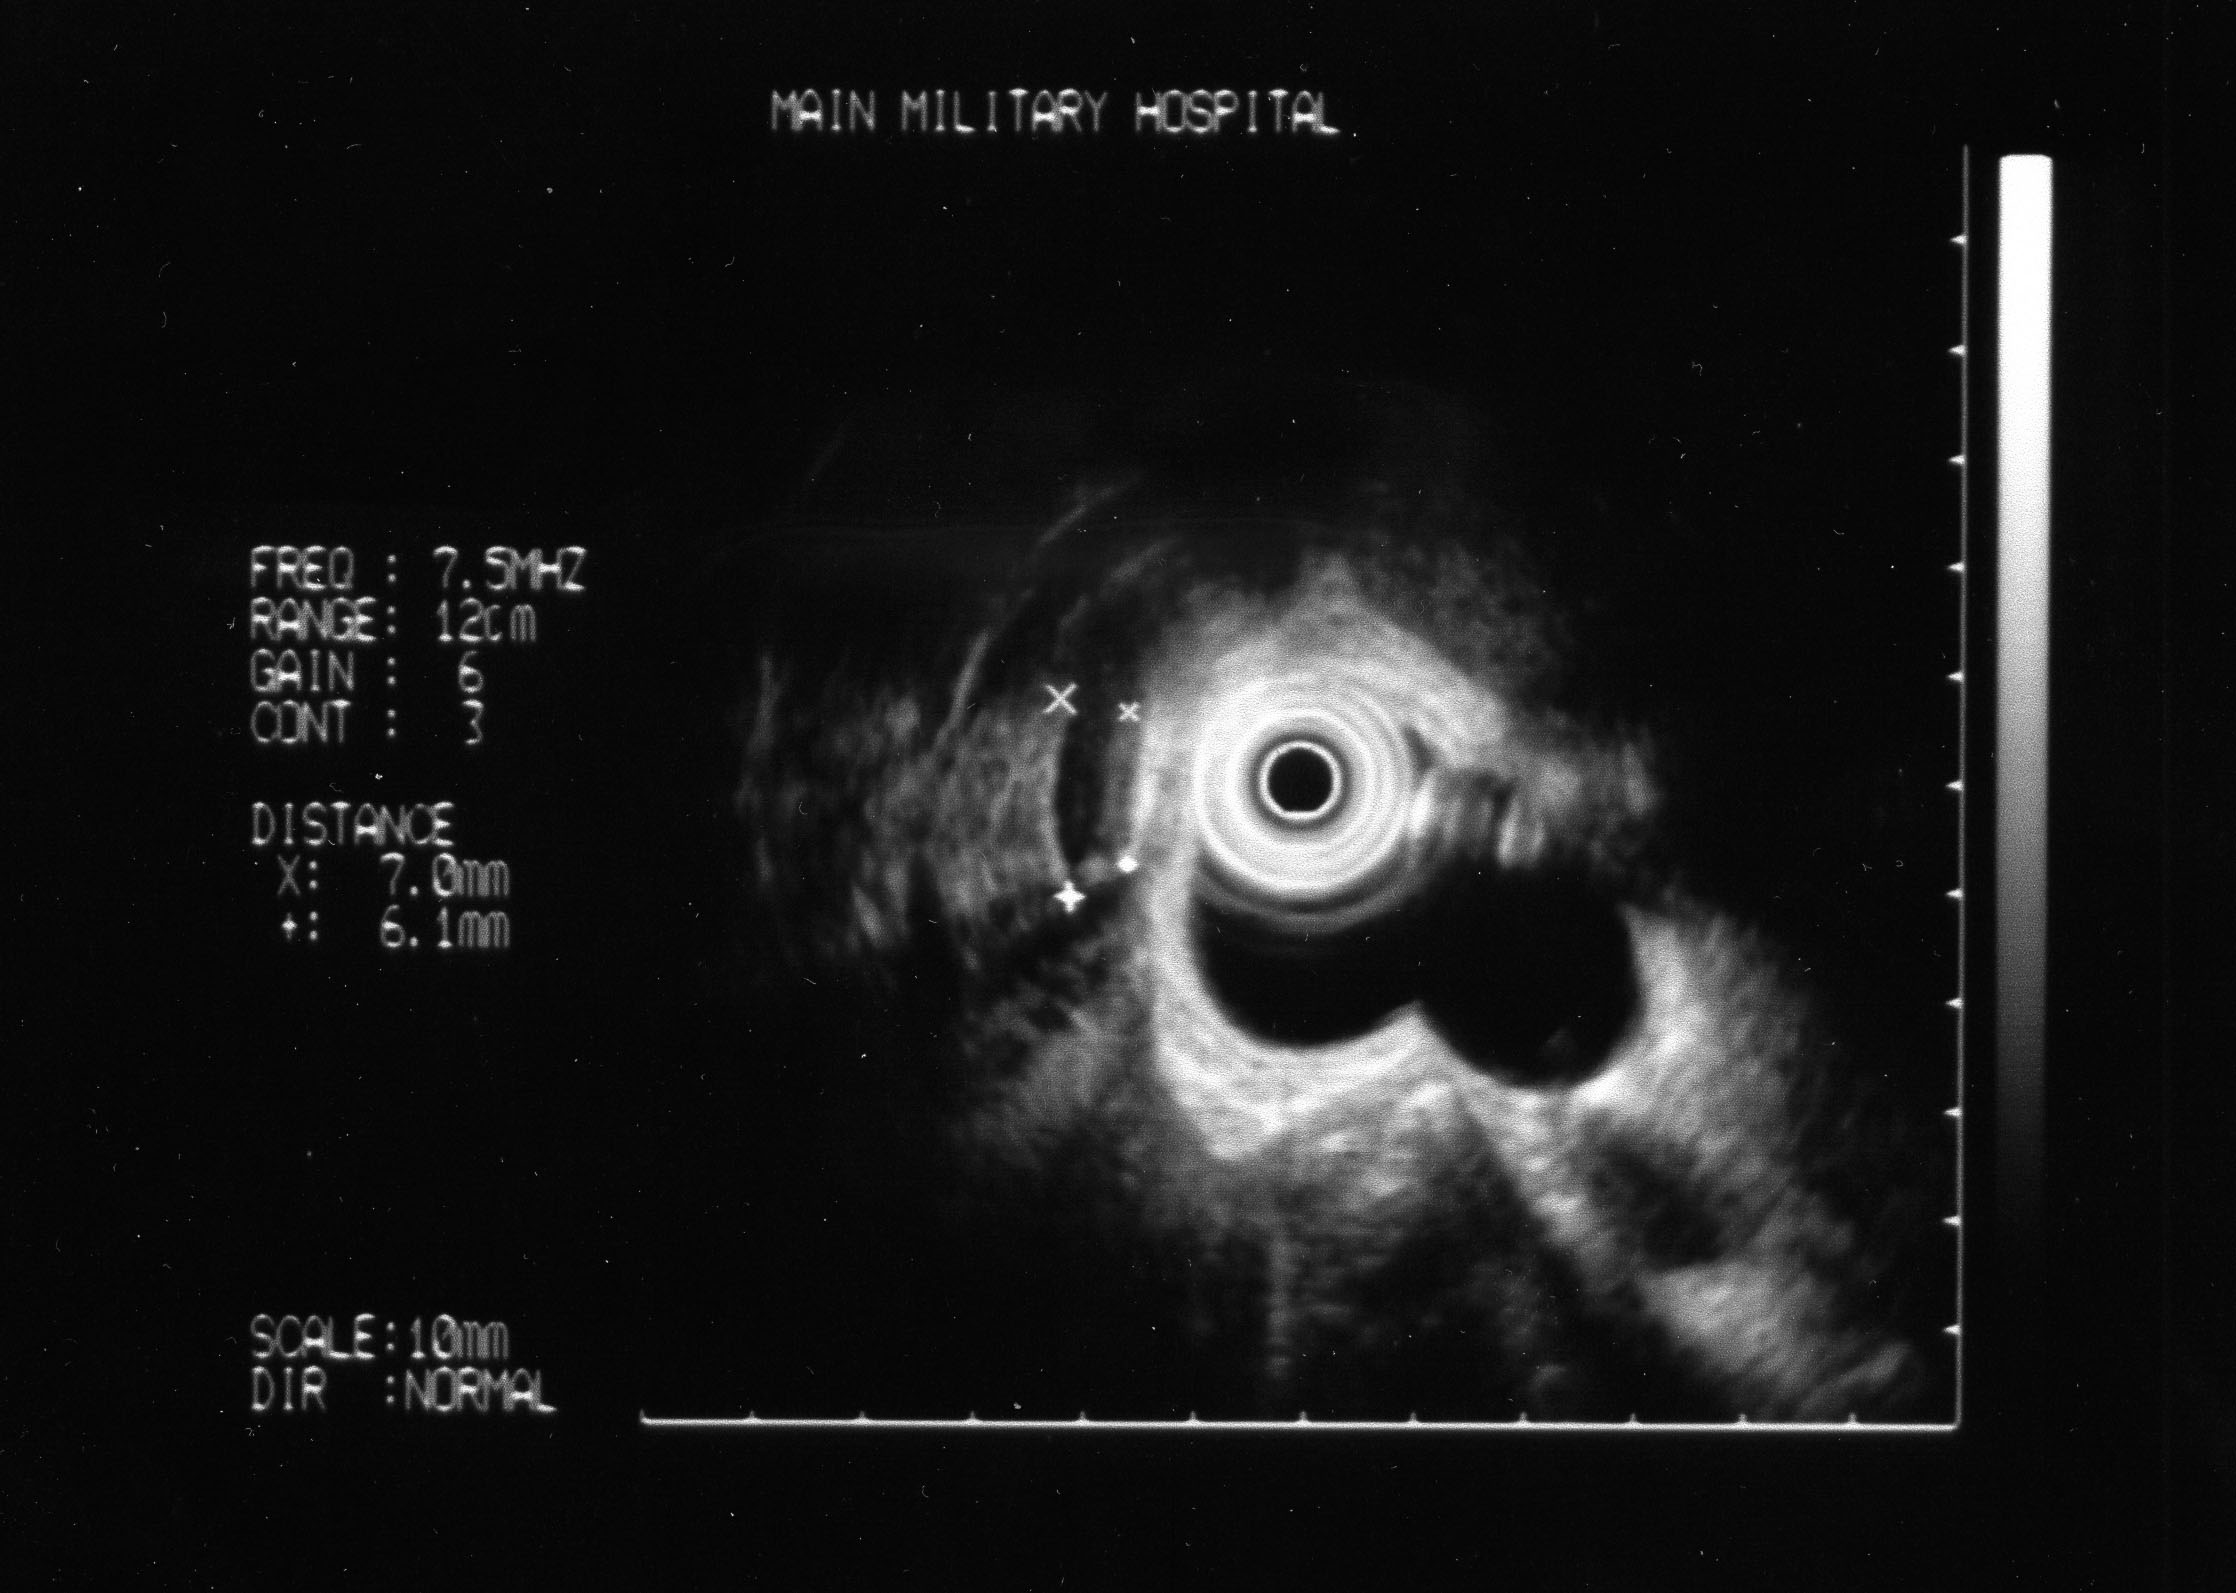

Чутливість ЕУС у діагностиці холедохолітіазу є високою не тільки при діаметрі конкремента >10 мм (100%), а також при діаметрі до 5 мм та 5-10 мм − 94,7 та 96,8% відповідно, тоді як чутливість ЧУЗД при діаметрі конкремента ЗЖП до 5 мм, 5-10 мм та більше 10 мм відповідно становить 14,7; 23,4 та 54,0%, є незадовільною (рис. 1).

Рис. 1. Частота виявлення холедохолітіазу за допомогою ЧУЗД (n=118) і ЕУС (n=72) у хворих на холецистит залежно від діаметра конкремента.

З

а

допомогою ЕУС можна виявити конкремент

ЗЖП діаметром навіть 2 мм (рис. 2).

Рис. 2. Ендоскопічна ультрасонографія. Діаметр ЗЖП – 6 мм, конкремента − 2 мм.